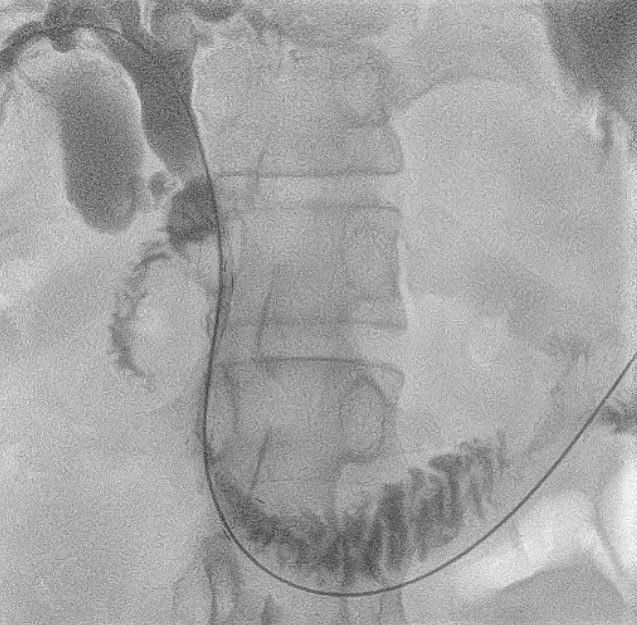

– Placement of a 10mm x 80mm SEM biliary stent with external drainage at the confluence.

– Post-stenting cholangiogram displayed smooth contrast flow into the duodenum.

The post-procedure recovery was smooth, with notable improvements in bilirubin levels and confirmed stent expansion during follow-up. This case highlights the pivotal role of Interventional Radiology in addressing intricate oncologic biliary obstructions, providing palliative care and enhancing the quality of life for patients with advanced malignancies.